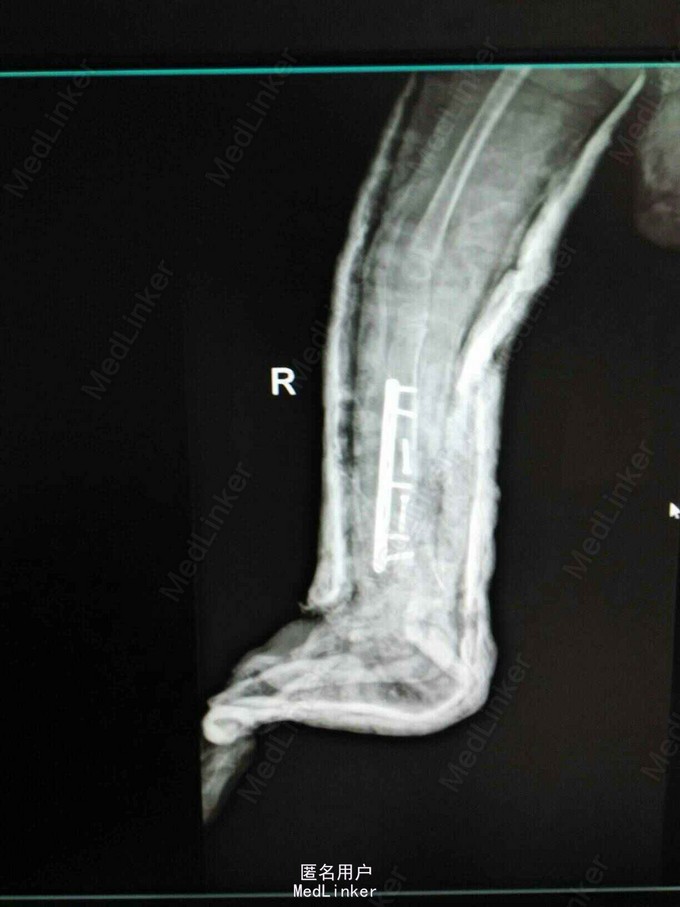

患女1岁8个月,患者母亲诉小孩出生时右小腿畸形,1岁时学走路跌倒后哭闹数天,小腿肿胀去医院检查示右胫腓骨折,稍做固定,1岁3个月时复查骨折未愈合,考虑先天性胫骨假关节,行手术治疗,现术后5个月复查未愈。目前小儿不能行走。

右下肢短缩约2cm,右小腿畸形,肌力检查不配合,

神经纤维瘤病,先天性胫骨假关节。该患者经过讨论及与家属多次沟通愈后情况,行病灶切除,取母体骨移植,AO锁定钢板内固定,暂时管型石膏外固定,并订制支具